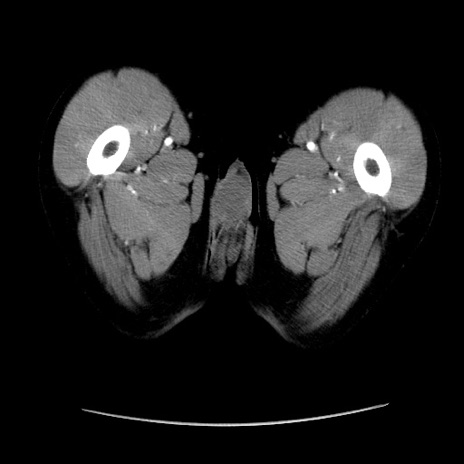

症例37(横断像)

【症例】40歳代 男性

【主訴】腹痛

【現病歴】4時間ほど前に電車に乗車中に臍部上より腹痛出現。徐々に増悪し起立困難となり、救急外来受診。生ものは数日食べていない。今朝お雑煮を食べた。

【身体所見】BT 36.8℃、BP 117/84mmHg、HR 91/min、SpO2 97%、苦悶様、腹部:臍上部広範囲圧痛あり、反跳痛±

【データ】WBC 8100、CRP 0.03